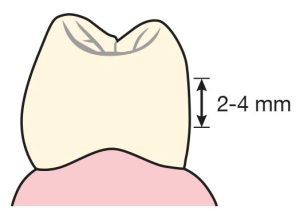

This guide plane surface should form a curvature with an occlusogingival height of 2-4 mm and not a flat surface when viewed occlusally (Figures 10-21).

On the lingual surfaces of the abutment teeth, the occlusogingival height of the guide plane is 2-4 mm. It is located in the middle third of the clinical crown when viewed from the mesial or distal aspect (Figures 10-24).